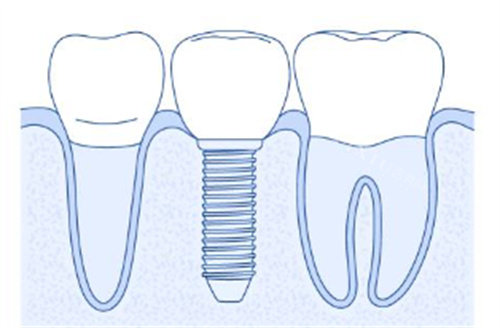

意大利比多亚种植体(Bidoia)在口腔种植领域具有一定的应用价值。该种植体系列采用锥形外观设计,内部为六角结构,并经过双重密封连接技术处理,这些设计特点有助于降低细菌堆积和骨吸收的可能性。

比多亚种植体的设计包含几个关键特点。首先,它采用15°莫氏锥度连接技术,这种设计能有效降低中央螺丝断裂的风险。其次,该种植体运用平台转换技术,通过内八角锥形结构,增强了基台与种植体之间的连接稳定性。此外,种植体表面经过特殊处理,增加了表面粗糙度,这有助于提升初期稳定性并促进骨结合过程。

综合来看,比多亚种植体通过其特定的设计特点,在口腔种植领域提供了一种可行的解决方案。其结构设计和表面处理技术有助于提升临床结果,而相对合理的价格区间也为患者提供了更多选择空间。在实际应用中,需要根据患者的具体情况和医生的特色判断来决定是否适合使用该种植体系统。